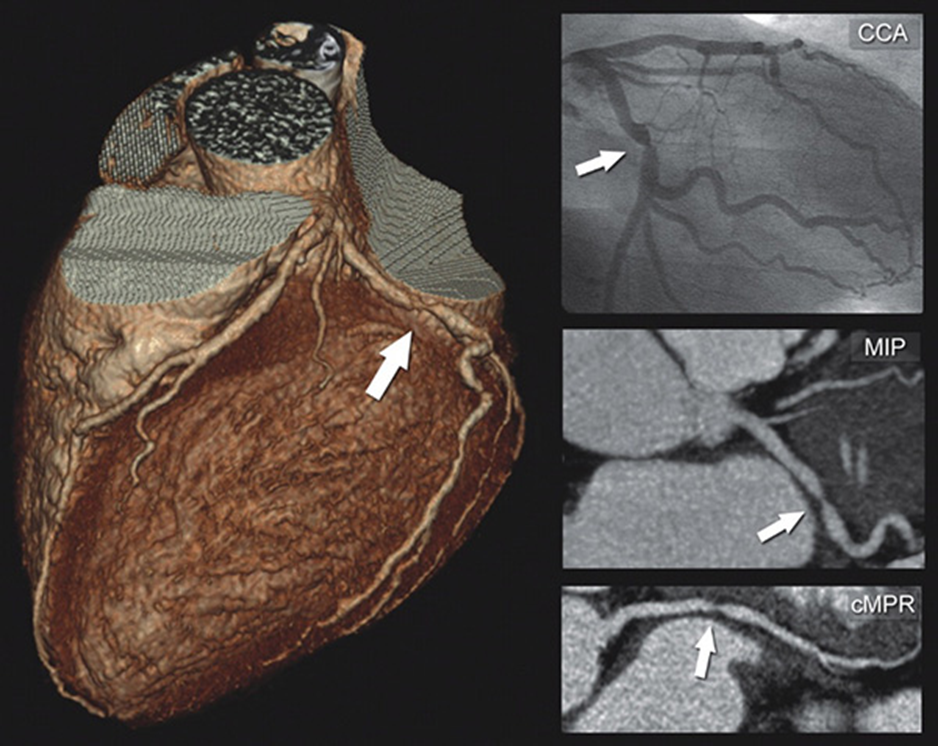

سي تي آنژيوگرافي قلب روشي براي مشاهده وضعيت عروق کرونري قلب است. اين عمل بدون نفوذ به پوست و بدون قرار دادن وسيله‌اي در داخل رگ‌هاي خوني انجام مي‌شود. در اين روش از سي تي اسکن همراه با یک ماده تأمین کننده کنتراست که به داخل یک سیاهرگ تزریق می‌شود، استفاده می‌گردد تا سرخرگ‌هایی که وظیفه خون‌رسانی به قلب را بر عهده دارند، به وضوح قابل مشاهده شوند. تصویری که به وسیله این روش تولید می‌شود، یک تصویر زنده و سه بعدی است که نحوه رسیدن خون به ماهیچه‌های قلب شما را با وضوح و جزئیات کامل نشان می‌دهد

سی تی آنژیوگرافی قلب می‌تواند شدت استنوز یا همان تنگ‌شدگی سرخرگ‌های کرونری را با دقت بالایی نشان دهد. همچنین این روش قادر است هر گونه ناهنجاری و عوارض غیر طبیعی در عروق کرونری را مشخص نماید. علاوه بر آن می‌توان از این روش برای بررسی نحوه کارکرد عروق کرونری پیوندی هم استفاده کرد. به طور کلی سی تی آنژیوگرافی قلب می‌تواند برای انجام مراحل درمانی در بیماران زیر کارایی داشته باشد:

سی تی انژیوگرافی یک روش غربالگری است و دقت آن بیشتر در کسانی است که بیماری کرونر ندارند و سی تی آنژیوگرافی نرمال می شود که در این گروه با دقت خوبی می توان گفت بیماری وجود ندارد ولی اگر این روش تنگی عروق را نشان دهد قطعی نبوده و نیاز به آنژیوگرافی برای هر گونه آنژیوپلاستی یا عمل جراحی باقی می ماند.

در یک کلام  آنژیوگرافی عروق کرونر روش نهایی تشخیص عروق کرونر بوده و دقت آن بسیار بیشتراز سی تی آنژیوگرافی است ولی سی تی آنژی هم موارد استفاده خود را بیشتر در کسانی که شانس بیماری کرونر کم تا متوسط است را دارد و پزشک شما بر اساس شرایط شما بهترین را برای شما انتخاب می کند